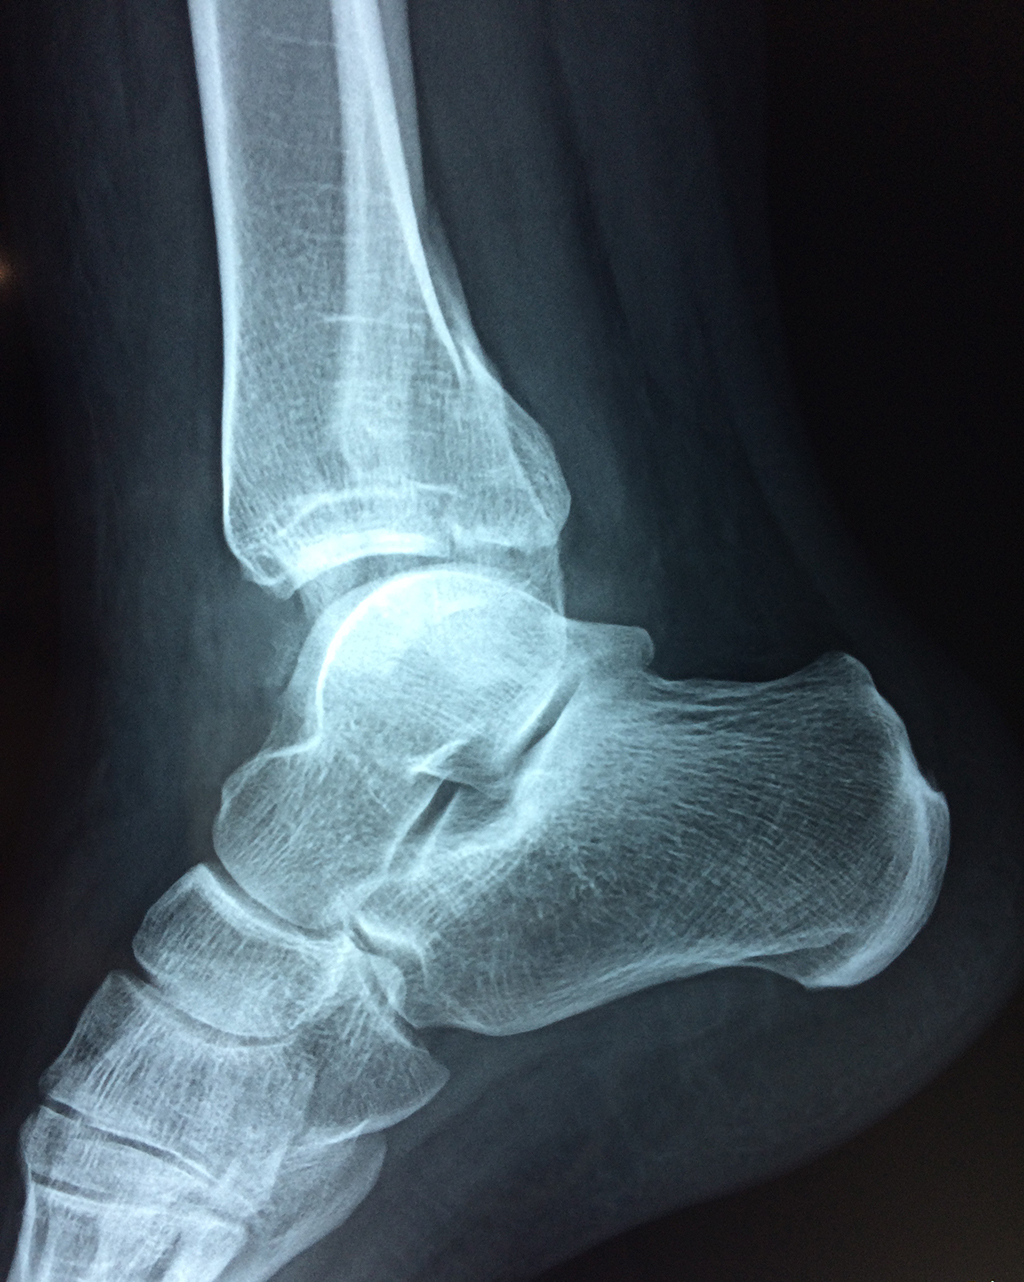

Una fractura de tobillo es la rotura de uno o más de los huesos del tobillo. Estas fracturas pueden ser:

- Parciales (el hueso está sólo parcialmente fisurado, no del todo).

- Completas (el hueso está perforado y está en 2 partes).

- Producirse en uno o ambos lados del tobillo.

Algunas fracturas de tobillo pueden requerir cirugía si:

- Los extremos de los huesos están desalineados entre sí (desplazados).

- La fractura se extiende hasta la articulación del tobillo (fractura intra-articular).

Cuando se necesita cirugía, es probable que esta implique el uso de clavijas de metal, tornillos o placas para sostener los huesos en su lugar mientras la fractura se consolida. Los elementos de soporte pueden ser temporales o permanentes.